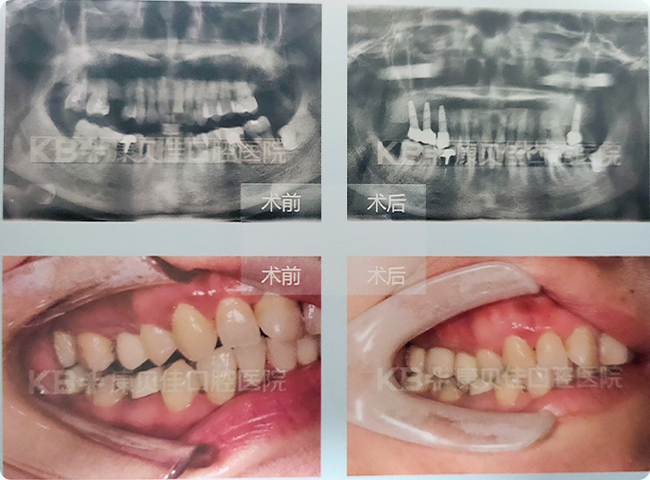

柏女士 72岁

没种牙之前连菜叶都要剁碎了吃,说话时也经常捂着嘴巴,生怕活动假牙会掉出来,更不好意思参加社交活动。在康贝佳采用”即刻用’种植牙技术恢复了全口牙后,当天晚上回家就吃了牛肉炒豆芽。现在想吃什么就吃什么,生活质量提高了,整个人也变得自信爱笑了!

治疗方案:

上颌种植7颗恢复半口 下颌种植6颗恢复半口